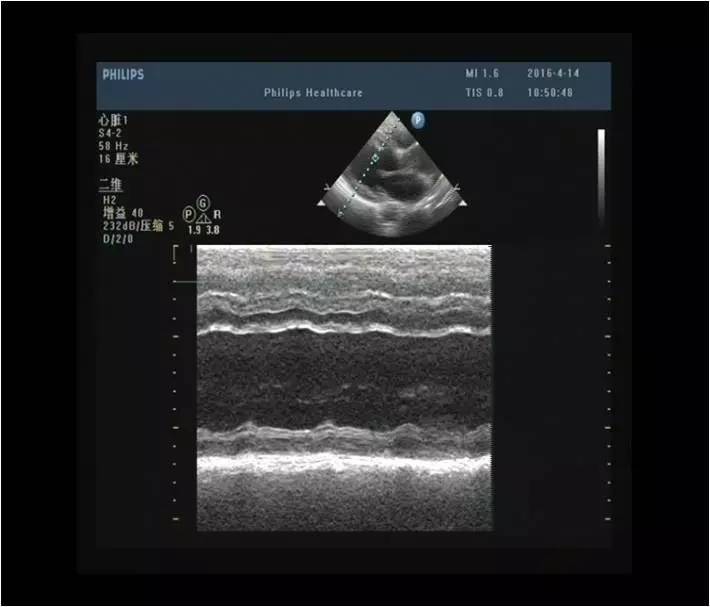

诊断结论:左房高值,左室增大,心功能:EF:28%(Simpson法),室壁运动普遍明显减弱,收缩功能测值明显减低。

AO窦部:42mm AAO:38mmLA:31mm LV:DM:48mm SM:35mmPA:22mm RA:26mm RV:26mm IVS:14mm LVPW:12mm

心功能:EF:51%;FS:27%

a.主动脉窦部及升主动脉内径增宽

b.左室壁增厚、运动不协调

c.二尖瓣、三尖瓣轻度返流

d.主动脉瓣轻-中度返流

e.左室舒张功能减退、收缩功能测值偏低